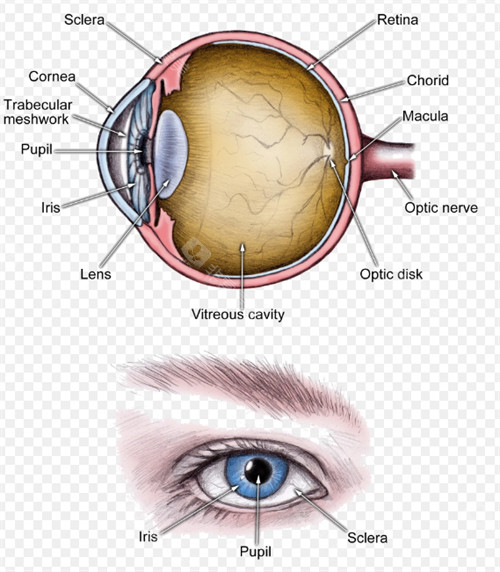

医学层面,申请者需经专科诊断确诊为白内障,且裸眼视力≤0.3或矫正视力<0.5,这一标准是判断手术必要性的核心依据。同时需排除相关禁忌症,例如活动性眼部感染、未控制的全身性疾病等。

特殊患病群体需提前完成基础治疗,如合并糖尿病视网膜病变的患者,需先接受眼底激光治疗,待病情稳定后再申请白内障手术;青光眼、视网膜脱离等眼部并发症患者,需先解决原发疾病,方可进入申请流程。